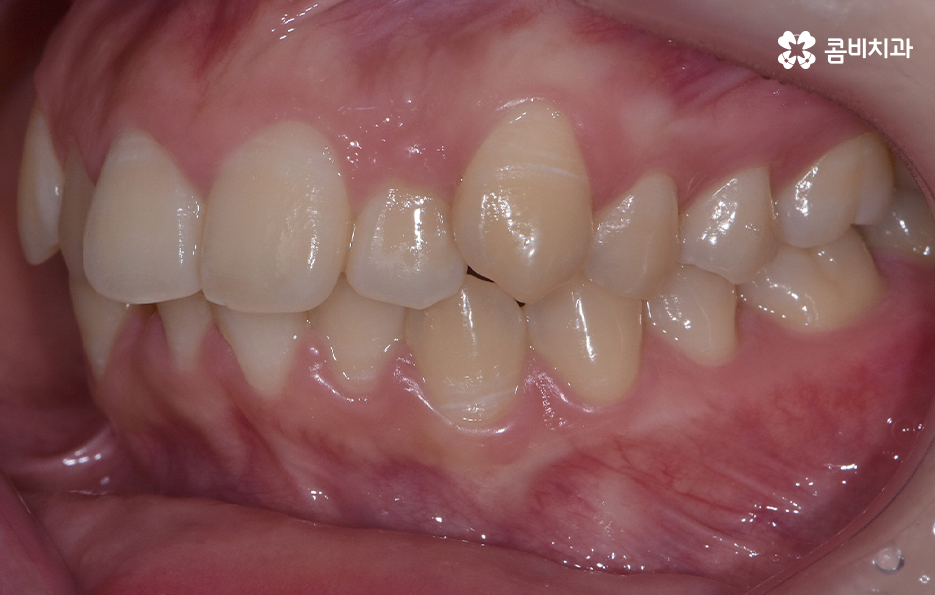

오늘 덧니 비발치 교정 사례로 보시는 환자분의 경우에는 윗니와 아랫니 앞니 부분에 조금씩 덧니가 있는 상태로 덧니를 제외하면 대체적으로 치열 상태는 고른 편이며 덧니 교정 사례 중에서는 돌출입도 함께 개선해야 하는 경우가 많지만 위 환자분의 경우에는 돌출입의 정도가 양호했고 입술라인 역시도 정상 범위에 가까웠기 때문에 발치를 필요로 하지 않았지만 치아의 이동 공간과 보다 자연스러운 입술라인 그리고 얼굴형과의 조화를 고려하여 악궁 확장과 어금니 후방 이동을 적절히 활용하여 교정 치료가 진행되었다고 볼 수 있어요